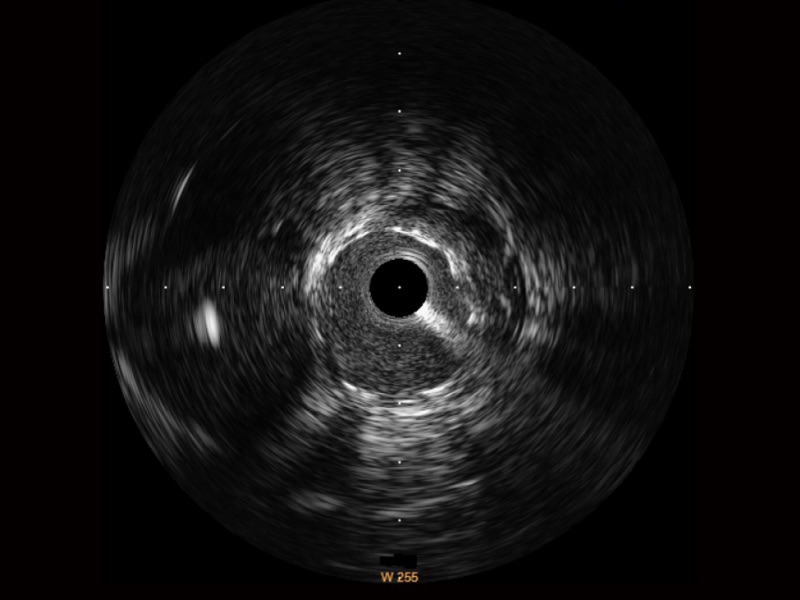

单晶超宽频IVUS VS 传统陶瓷材料IVUS

新葡的京集团8814检测站超宽频成像技术覆盖20-80MHz1或20-90MHz2频率范围, 提供优异的分辨力同时也保证充足的穿透深度

对比传统IVUS导管成像,新葡的京集团8814检测站宽频IVUS图像的近场支架梁显影更细腻,远场中膜外血管仍清晰可辨,兼顾远中近,兼顾分辨力与穿透深度